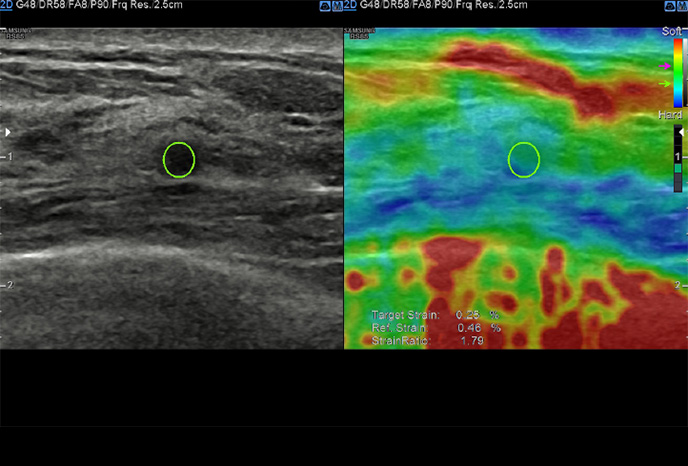

S-Shearwave Imaging ™

Neinvazivní metoda kvantifikace tuhosti tkáně

S-Shearwave Imaging ™ umožňuje neinvazivní hodnocení tuhosti tkáně / lézí v prsu a játrech, poskytnutím pokročilé úrovně diagnostických informací. Barevně mapovaný elastogram, kvantitativní měření (inkPa nebo m / s), možnost duálního zobrazení a uživatelem volitelné funkce ROI (pozice a velikost) jsou obzvláště užitečné pro přesnou diagnostiku onemocnění prsu a jater.